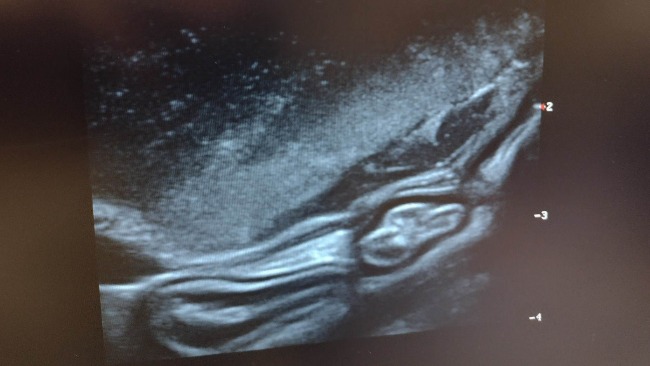

Dziś Kubuś miał również kolejne badanie USG, które wykazało bardzo duży osad w pęcherzu. Nerki w stanie opłakanym ...